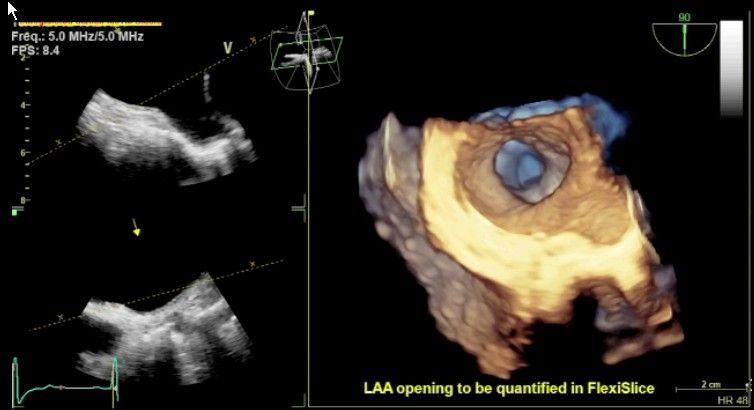

健康+医学 Transesophageal Echocardiography Transesophageal Echocardiography (TEE) | Heartplaceの詳細情報

Transesophageal Echocardiography (TEE) | Heartplace。PDF) Transesophageal Echocardiography in Clinical Practice。Transesophageal Echocardiography | Circulation。

Transoesophageal Echocardiogram - YouTube

題名:PracticalApproachtoTransesophagealEchocardiography,4thed.

著者:A.C.PerrinoJr.&S.T.Reeves(eds.)

出版社:WOLTERSKLUWER

ISBN:978-1-4963-8347-1

ページ数:643pp.

出版年:2020年

定価24,739円(本体22,490円+税)

題名:PracticalApproachtoTransesophagealEchocardiography,4thed.

著者:A.C.PerrinoJr.&S.T.Reeves(eds.)

出版社:WOLTERSKLUWER

ISBN:978-1-4963-8347-1

ページ数:643pp.

出版年:2020年

定価24,739円(本体22,490円+税)